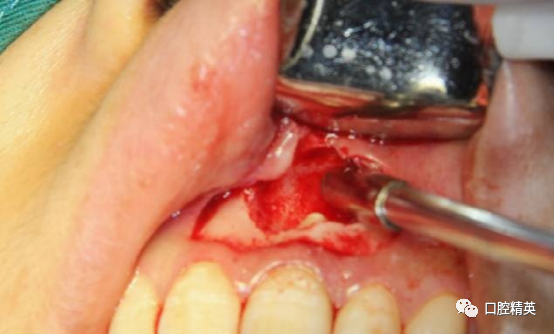

改良梯形瓣切开,范围要充分

保留美学区域软组织及其附着

边角区轻柔翻全厚瓣,始终以轻柔动作处理软组织瓣并保湿。由两侧向中上方向翻开。

术前检查已知唇侧骨开窗,囊壁与软组织瓣会出现粘连,采用锐性分离,轻柔分开组织瓣并彻底清理瓣内侧。